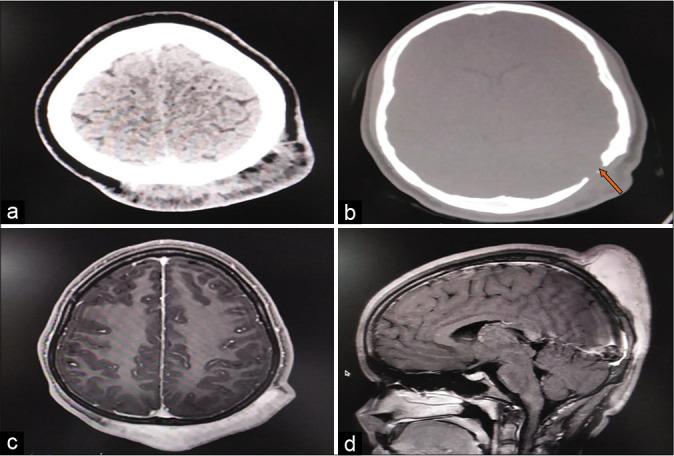

An 18-year-old woman presented with a history of rapidly progressive painless large swelling over the bilateral parieto-occipital region of scalp. It was soft and boggy with brownish discoloration of overlying skin. Imaging study showed brilliantly enhancing diffuse lesion involving the bilateral parieto-occipital region of scalp and extending into the extradural region. She underwent excision of lesion. Postoperatively, she developed flap necrosis and it was allowed to heal with the secondary intention. The biopsy findings were consistent with neurofibroma. The patient is on regular follow-up, without any evidence of recurrence at 1 year.

https://cdn.ncbi.nlm.nih.gov/pmc/blobs/9023/7568129/78d415cc1733/SNI-11-313-g001.jpg